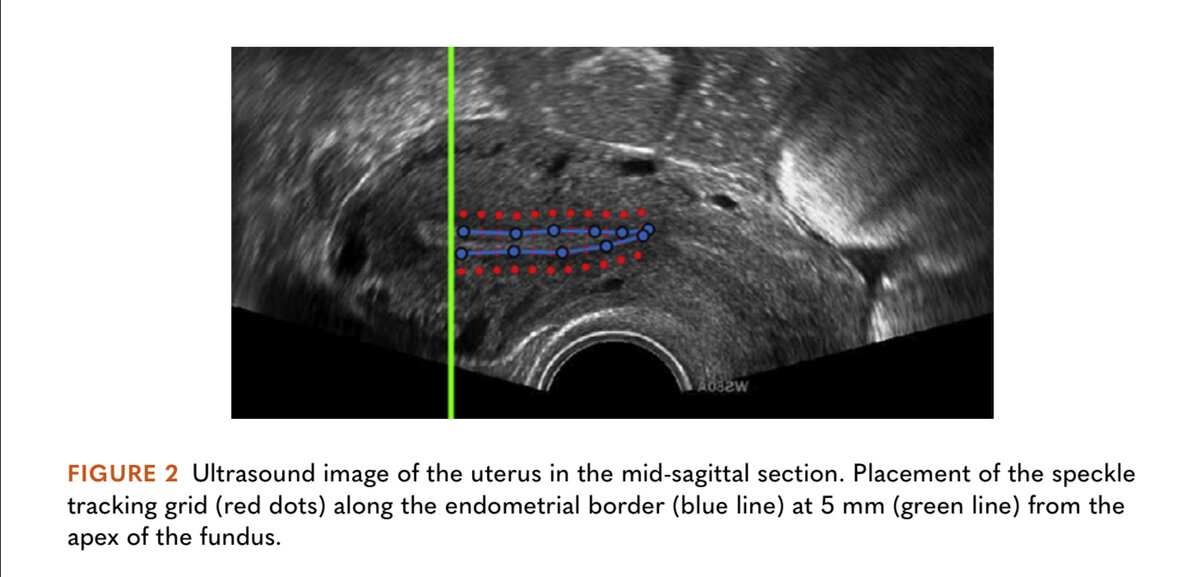

Матка в сагиттальном разрезе. Красные точки-это спеклы вдоль линии эндометрия (синие точки).

Для каждой записи ультразвука сетка отслеживающих маркеров вручную располагалась вдоль эндометрия, который является наиболее сократительно активной частью матки. Маркеры размещали на расстоянии 5 мм друг от друга вдоль границы эндометрия. Маркеры были соединены попарно, и между каждой парой были получены сигналы расстояния и деформации как в продольном, так и в радиальном

направлениях (рис. 3)